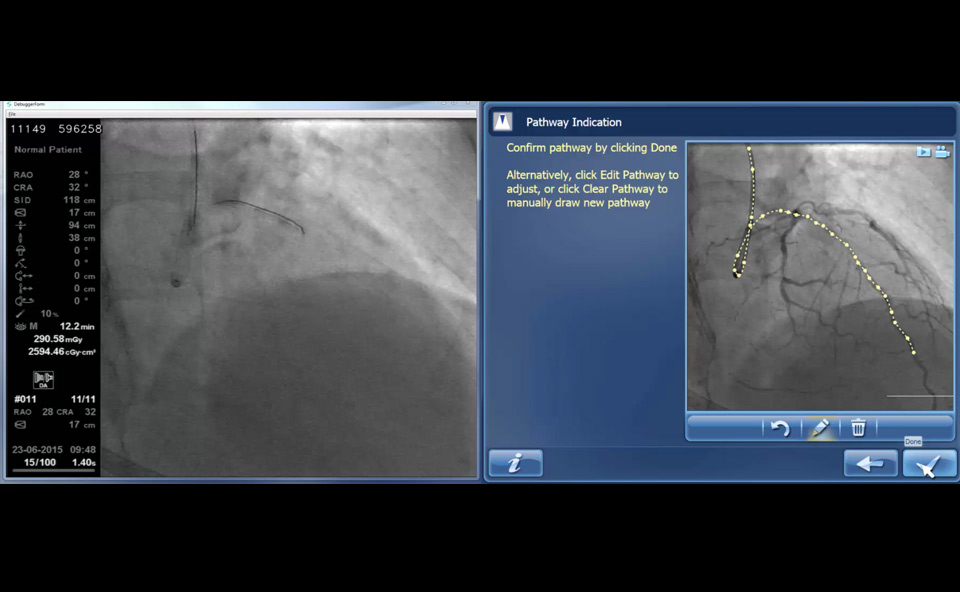

Die iFR Ko-Registrierung ordnet bildlich den iFR-Verlust entlang der Gefässdarstellung im Angiogramm zu und hebt so ischämieverursachende Gefässabschnitte hervor.

Die iFR Ko-Registrierung ist für die Distanz kalibriert, so dass Sie mit einem einfachen manuellen Rückzug die Messungen im Angiogramm sowie auf der Trendkurve vornehmen können.

„Click and drag“-Messungen helfen bei der Planung der Prozedur